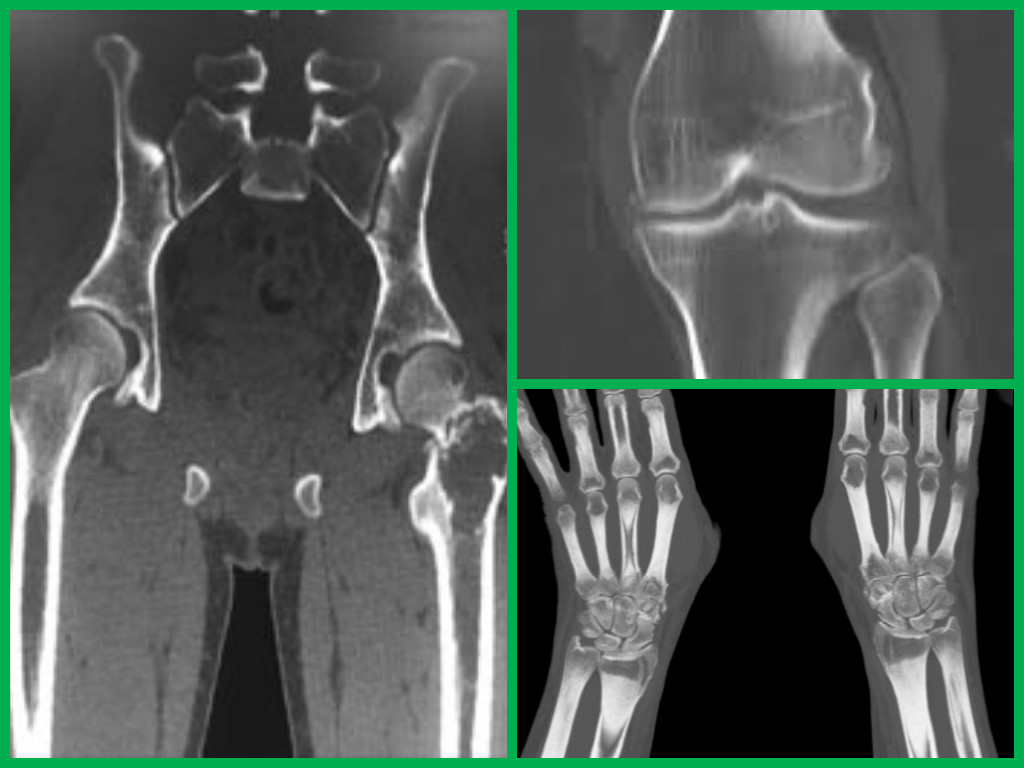

Компьютерная томография – это рентгеновский метод, который хорошо визуализирует костные и плотные хрящевые ткани. Разрешения современных мультиспиральных томографов (МСКТ) достаточно для изучения костной структуры. В клиниках Москвы и Санкт-Петербурга установлено более 50 томографов, поэтому сложностей с выполнением КТ сочленений, суставов, костей у местных жителей не возникает. Рассмотрим подробнее возможности метода.

КТ суставов считается надёжным, наиболее информативным методом исследования, путём которого изучают и оценивают структуру суставных тканей с высокой точностью. Такая томография суставов позволяет производить снимки костных сочленений в разных плоскостях. Благодаря этому увеличиваются возможности изучения проблемных зон, а врачу становится легче установить диагноз и назначить правильное лечение.

КТ назначают хирурги, ревматологи, травматологи для уточнения или установления диагноза. Путём этого метода подтверждают наличие артроза, артрита, остеомиелита, а также обнаруживают инородные предметы или образования в теле. Томография способна определить объём суставной жидкости, обнаружить места скапливания крови и различные аномалии в развитии суставов.

Исследования КТ:

- КТ коленного сустава проводят для диагностики травм, артритов, онкологических процессов. На нашем сайте вы узнаете, какова стоимость кт коленного сустава в разных клиниках в Москве.

- КТ тазобедренного сустава предназначено для определения диаметра головки бедра, а также на каком расстоянии от неё находиться впадина подвздошной кости. Также определяют местонахождение инородных тел, мелких кусков раздробленной костной ткани, воспалительные очаги.

- Когда исследуют локтевой сустав, то выявляют свежие или старые травмы локтя, опухоли, артроз, метастазы, ревматические изменения или прочие заболевания.

- При исследовании плечевого сустава выявляют онкологические или воспалительные заболевания, тщательно изучают травмы и структуру тканей.

Также проводят кт голеностопа и височно-нижнечелюстного сустава (ВНЧС). Чтобы точно исследовать голеностопный сустав, процедуру проводят на обеих ногах одновременно. Это важно для сравнения аномалий в строении суставов и прочих их особенностей для постановки безошибочного диагноза.

Этот метод высоко цениться специалистами за качество снимков и безошибочность получаемых результатов. В сравнении с МРТ его целесообразнее проводить от при травмах, внутрикостных опухолях, дегенеративных патологиях. Это обосновано тем, что процедура МРТ более сильна в диагностике связок, мягких тканей и пр. К тому же, цена кт суставов ниже чем стоимость мр-томографии.